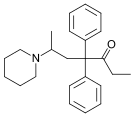

Amidones

Structures

| Amidones | ||||